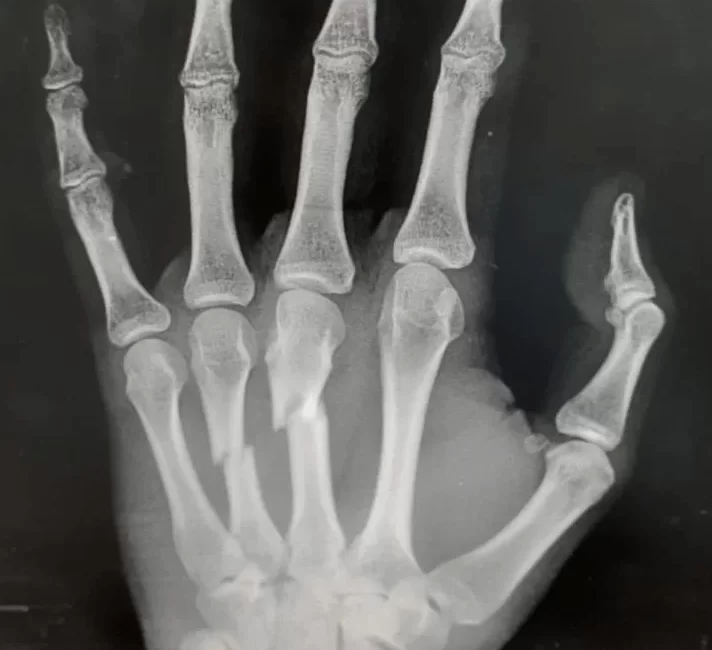

Suspeita de fratura na mão? Conheça os sintomas e saiba quando procurar ajuda!

Se você sofreu uma lesão na mão e está preocupado com a possibilidade de uma fratura, é crucial estar atento aos sintomas e procurar um especialista em cirurgia da mão. Abaixo, listamos os principais sintomas de uma fratura na mão:

- Deformidade: A presença de deformidades na mão, como um dedo torto ou uma protuberância óssea, pode indicar uma fratura.